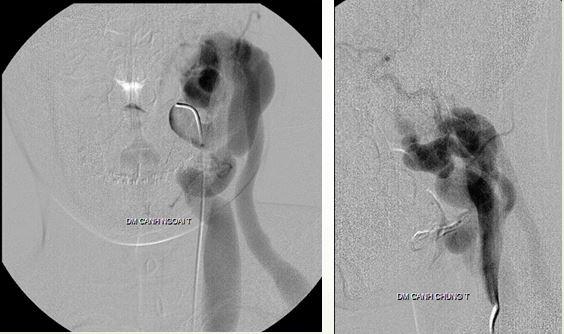

Can thiệp cứu bệnh nhân bị tai nạn giao thông, máu mũi chảy ồ ạt do vỡ xoang bướm

Một trường hợp mà tất cả phòng cấp cứu đều có thể gặp, đó là một bệnh nhân nam 29 tuổi, chạy xe moto tông vào cột điện, nhập viện điều trị các chấn thương vùng mặt (không có chấn thương sọ não). Nhưng khi bác sĩ nội soi tai mũi họng thì đột ngột chảy máu ồ ạt. Ảnh chụp CT cho thấy bệnh nhân vỡ xoang bướm, máu tụ rất nhiều trong xoang bướm, bệnh nhân được chuyển sang phòng DSA.

Hình ảnh DSA có giả phình trong xoang bướm gây chảy máu mũi họng ồ ạt

Bệnh nhân sau can thiệp

BS Cường nhấn mạnh: các phòng cấp cứu nếu tiếp nhận bệnh nhân chảy máu mũi ồ ạt thì nên chụp kỹ vùng xoang bướm, nếu thấy xoang bướm có máu thì nhanh chóng chuyển bệnh nhân qua phòng DSA can thiệp cấp cứu.